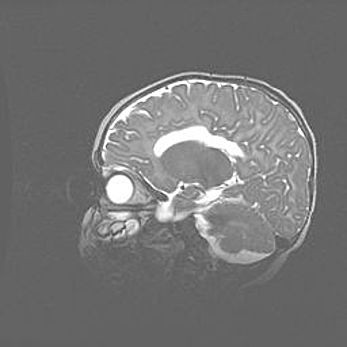

Церебральная ишемия II.

Возраст: 5 дней

Вес: 3400 г

Пол: женский

Окружность головы: 35 см

Срок гестации: 39 недель

Церебральная ишемия – это заболевание, характеризующееся недостаточностью (гипоксией) либо полным прекращением (аноксией) снабжения мозга кислородом по причине закупорки одного или нескольких сосудов. Это приводит к  что метаболическим расстройствам различной степени тяжести в тканях головного мозга, развитию коагуляционных некрозов и гибели нейронов.